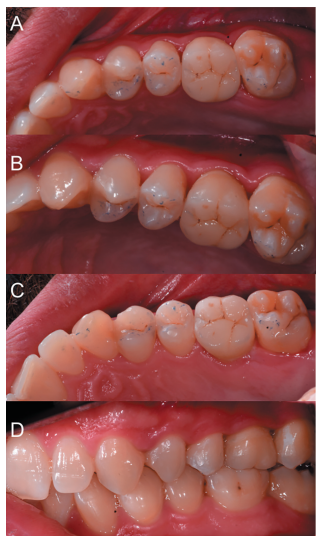

Transcurridos 2 meses se realizó una nueva revisión clínica (Figura 17) y radiográfica mediante radiografía periapical (Figura 18), procediéndose a retirar la ferulización. A los 3 meses se realizó otra revisión clínica (Figura 19) y radiográfica mediante radiografía periapical paralelizada (Figura 20), donde se puede observar una adecuada formación ósea alrededor del diente trasplantado.

A los 5 meses se talló el diente autotrasplantado en sus caras oclusal, vestibular, palatina e interproximales, para tomar después una doble impresión de silicona pesada y fluida en un paso (Elite HD®, Zhermack, Rovigo, Italia), y posteriormente pedir al laboratorio una incrustación de disilicato de litio (Figura 21).

Se fresó la incrustación de disilicato de litio, que se preparó en clínica mediante un grabado con ácido fl uorhídrico y silano (Ultradent®, Madrid, España) (Figura 23). Después se realizó un aislamiento absoluto de los dientes 2.5, 2.6 y 2.7 mediante dique de goma, y se preparó el diente 2.6 con ácido ortofosfórico, y adhesivo de autograbado, para después cementar la incrustación con cemento de resina de polimerización dual (3M Relyx Unicem®, Minnesotta, EEUU) (Figura 24). Tras polimerizar durante tres segun dos, se retiraron los excesos de cemento, se terminó de polimerizar y se retiró el dique de goma para ajustar la oclusión (Figura 25) y hacer una radiografía periapical paralelizada de comprobación (Figura 26).

Los estudios clínicos publicados evalúan clínica y radiográficamente a los pacientes, mediante radiografías periapicales9,10,12,15,17,18 o mediante periapicales y radiografía panorámica4,13,14. En la radiografía periapical se pueden apreciar la presencia de áreas radiolúcidas, reabsorciones radiculares externas e internas, anquilosis y el estado de desarrollo radicular18, siendo fundamentales en la evolución de esta modalidad terapéutica. En el presente caso clínico se apreció de manera radiográfica un área radiolúcida alrededor del diente, que fue modificándose con el paso del tiempo, para conseguir una densidad ósea similar del hueso en contacto con el diente trasplantado, en comparación al hueso circundante. Asimismo, no se apreciaron lesiones apicales ni presencia de reabsorciones radiculares durante el tiempo de seguimiento.

Además, se obtuvo un buen resultado clínico y radiográfico, tras 5 meses de seguimiento, describiendo el paciente una buena función masticatoria y la ausencia de efectos adversos, que se describen en la literatura con una tasa del 4%, destacando entre ellos la anquilosis y la reabsorción radicular.